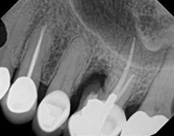

This patient presented with pain when chewing. Diagnostic testing was done and determined it was the lower molar. The diagnosis was: pulpal necrosis, symptomatic periradicular periodontitis. Root canal treatment was performed with laser disinfection. The tooth had a crown and we accessed the tooth through the crown. We saved the tooth and the crown.